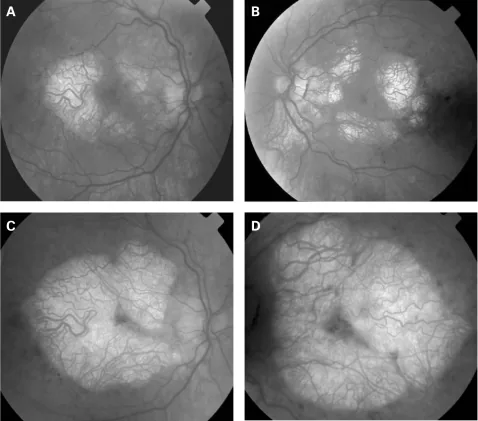

所見:両側性・対称的な視神経乳頭蒼白1)。遺伝学的に確認された小児・若年成人7例中6例(85.7%)で視神経萎縮を認めたとする報告もある。

注目点:視覚的に無症候な患者3例全例でRNFL・黄斑GCC菲薄化が検出された。

視覚的に無症候な患者でもOCT検査で網膜神経線維層や黄斑部神経節細胞複合体の菲薄化が検出される。潜在的な網膜神経細胞の脱落を反映しており、定期的な眼科フォローが推奨される。

網膜神経節細胞はエネルギー需要が高く、ミトコンドリア機能障害に対して脆弱である1)。視覚的に無症候な患者でもRNFL・GCCの菲薄化が検出されており、潜在的な神経細胞脱落が進行していると考えられる。